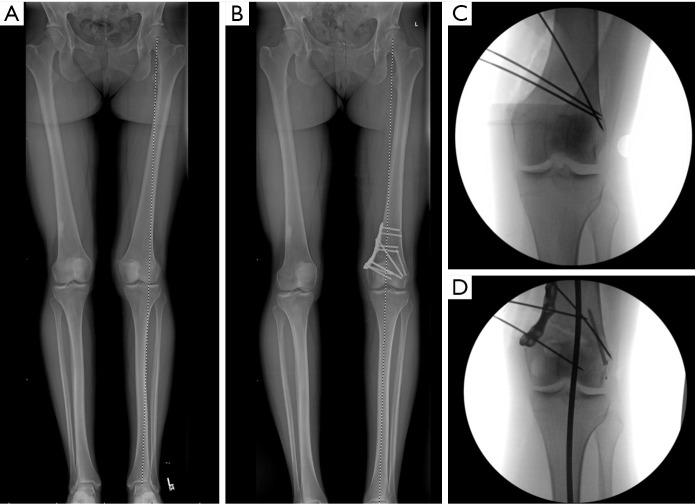

膝关节周围截骨术是一种有效的方法,通过纠正膝关节的整体排列来保护膝关节。虽然截骨术历来被用于治疗膝关节病理,但最近作为一种治疗策略重新引起了人们的兴趣,这种治疗策略可用于矫正关节位、韧带稳定和软骨保护。截骨术是纠正矢状面和冠状面排列的一种有效方法,可以保存和/或保护膝关节内侧、外侧和髌股间室的软骨,并改善膝关节韧带的稳定性。内侧开口楔形高胫骨截骨术(MOW-HTO)和外侧闭合楔形高胫骨截骨术(LCW-HTO)是矫正内翻畸形的常用截骨术,各有不同的适应症、手术技术和相关并发症。同样,股骨远端截骨术(DFO)在矫正内翻和外翻错位中起着至关重要的作用,在单独胫骨截骨术会导致关节线倾斜度过高(JLO)的情况下可能尤为重要。在单节段截骨不能提供最佳矫正的复杂情况下,可能需要双节段截骨来实现适当的机械轴修复,同时保持关节一致性。除了冠状面矫正外,矢状面截骨术越来越受到关注,以治疗韧带不稳定,特别是前后交叉韧带(PCL)缺陷。通过前闭合楔形或前开放楔形高位胫骨截骨术改变胫骨后斜率(PTS)可以改善前交叉韧带(ACL)和pcl缺陷患者的膝关节生物力学和稳定性。此外,胫骨结节截骨术(TTO)已成为一种重要的手术辅助治疗髌骨股骨错位和软骨保存策略。膝关节截骨术的目的是卸载受影响的腔室,保存和保护软骨和半月板,增强韧带的稳定性,从而推迟关节置换术的需要。因此,截骨术对于年轻和活跃的患者来说是一种有趣的手术。最近,随着对膝关节截骨术的重新关注,研究表明,截骨术在肢体对齐和软骨保护治疗中继续发挥关键作用。

Osteotomies around the knee are an effective method for preserving the knee joint by correcting overall alignment. Although osteotomies have historically been used in treatment of knee pathology, they have recently regained a renewed interest as a treatment strategy for alignment correction, ligamentous stability, and cartilage preservation. Osteotomies are a powerful way to correct alignment in both the sagittal and coronal plane to preserve and/or protect the cartilage in the medial, lateral, and patellofemoral compartments of the knee and improve the ligamentous stability of the knee. Medial opening wedge high tibial osteotomy (MOW-HTO) and lateral closing wedge high tibial osteotomy (LCW-HTO) are commonly performed osteotomies for correcting varus malalignment, each with distinct indications, surgical techniques, and associated complications. Similarly, distal femoral osteotomy (DFO) plays a critical role in the correction of both varus and valgus malalignment, and may be particularly important in cases where a tibial osteotomy alone would lead to excessive joint line obliquity (JLO). In complex cases where single-level osteotomy does not provide optimal correction, double-level osteotomy may be necessary to achieve appropriate mechanical axis restoration while maintaining joint congruence. Beyond coronal plane corrections, increasing attention has been given to sagittal plane osteotomies for managing ligamentous instability, particularly anterior and posterior cruciate ligament (PCL) deficiencies. Modifying the posterior tibial slope (PTS) through anterior closing wedge or anterior opening wedge high tibial osteotomy can improve knee biomechanics and stability in both anterior cruciate ligament (ACL) and PCL-deficient patients. Additionally, tibial tubercle osteotomies (TTO) have emerged as an important surgical adjunct in the treatment of patellofemoral malalignment and cartilage preservation strategies. The goal of knee osteotomies is to offload the affected compartment, preserve and protect cartilage and menisci, and enhance ligamentous stability, thereby delaying the need for arthroplasty. Therefore, osteotomies represent an intriguing procedure for young and active patients. Recently, with the renewed interest in osteotomy procedures about the knee, studies have demonstrated that osteotomies continue to play a critical role in treatments for limb alignment and cartilage protection.